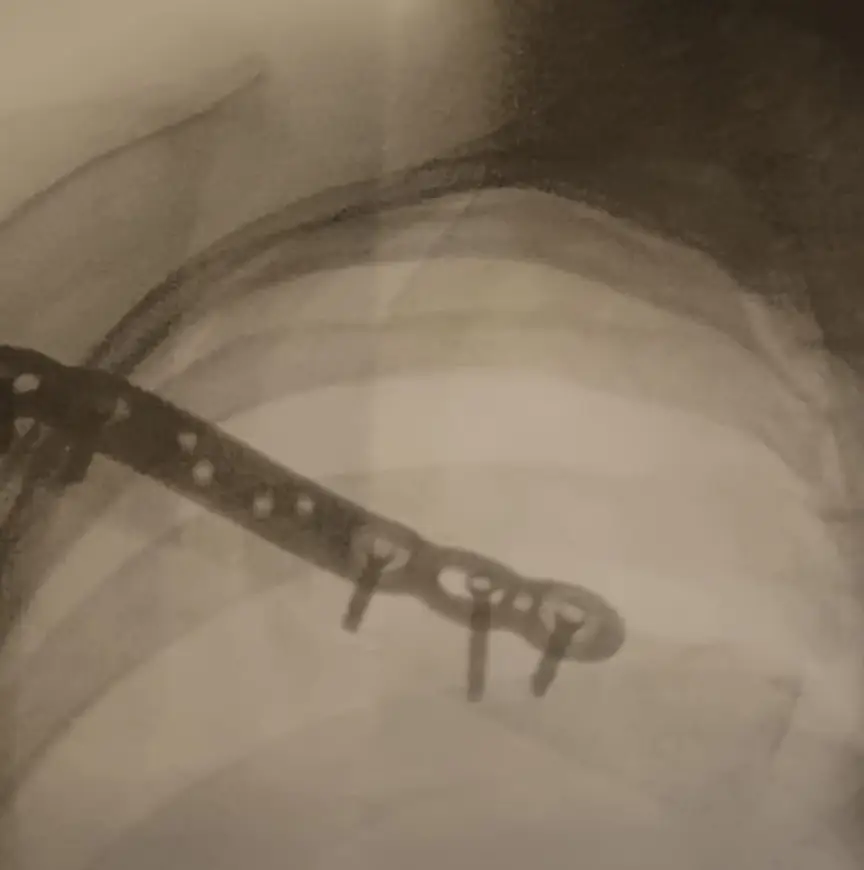

Het is nu ruim een week later, wanneer ze op gereserveerde toon haar toestand onder woorden brengt. “Het gaat.” De reden laat zich raden. De hersenschudding veroorzaakt zeurende pijn, maar het gebroken sleutelbeen – dat oorspronkelijk op natuurlijke wijze had moeten helen – is woensdag operatief onder handen genomen. “Ik ging naar het ziekenhuis voor een controlefoto, en een paar uur later lag ik op de tafel omdat het bot niet goed aan elkaar groeide. Stel: je legt twee wijsvingers op elkaar met een beetje overlap, en dan nog enkele millimeters ruimte ertussen. Dan heb je een idee hoe mijn sleutelbeen heeft gestaan….”

De zaak zit nu aan elkaar door middel van een plaatje. “Waarschijnlijk heb ik van deze blessure minder lang last dan van mijn hoofd. De pijn was in eerste instantie aardig verdwenen, maar sinds afgelopen zondag is het erger geworden. Dankzij de pijnstilling voel ik momenteel weinig. Eerlijk gezegd verwacht ik dat mijn hoofd me de grote beperkingen zal gaan opleggen.” Mossinkoff praat uit ervaring. Een dik jaar geleden is ze van haar mountainbike getuimeld, met een hersenschudding tot gevolg. Er zijn genoeg voorbeelden van sporters die zich te snel terug melden aan het front. “Het is zaak om vooral niet te snel te beginnen”, klinkt redelijk overtuigend. “En ook rustig op te bouwen. Niet te veel te doen.” Ze lacht zacht. “Dat kan lastig zijn, ja.” Want bij haar gaat het al snel...